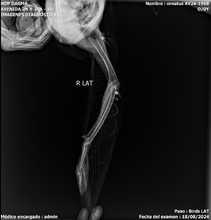

Un águila coronada afectada por perdigones fue rescatada en el parque El Ingen